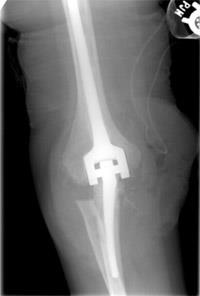

elbow joint replacement

X-ray of a patient who underwent elbow joint replacement.

In appropriately selected patients, the improvement in pain and function after a joint replacement can be dramatic. However, there are long-term functional limits — usually, you cannot lift more than 5 to 10 pounds with the treated arm — so the decision to have a total elbow replacement should be made carefully.